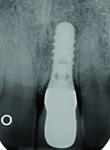

Six months after the bone block fixation ridge augmentation procedure (Figure 8), the screws were removed. Visualization of the area was accomplished by reflecting a full-thickness flap with releasing incisions. As sufficient bone volume was available, a two-stage implant placement protocol was followed to place the second endosseous implant (4.1-mm diameter regular neck [RN] 10-mm implant [Straumann AG]) with a cover screw in the area of the left maxillary central incisor (Figure 9). The patient continued to wear the IRPD as he healed uneventfully.

At the 21-month follow-up appointment, the implant and implant-supported crown (ISC) demonstrated no clinical signs of mobility, and there was no radiographic evidence of peri-implant radiolucency or marginal bone loss (Figure 11).